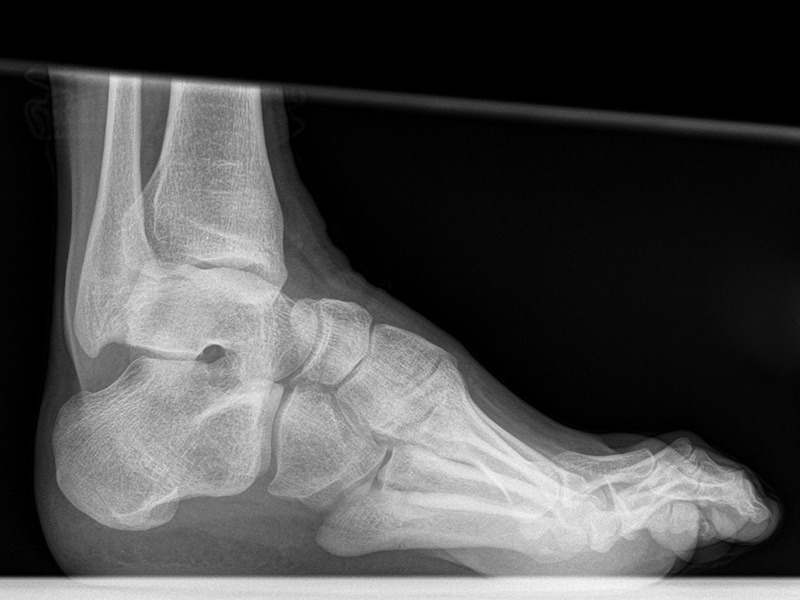

Bewegungsumfang oberes Sprunggelenk

Seitliche Aufnahmen des Sprunggelenks zur Beurteilung der Dorsalextension

Positionierung Variante 1:

• Der Patient steht, beide Beine sind geleichmäßig belastet.

• Das Knie wird maximal nach ventral geschoben. Zum Ausgleich kann der andere Fuß nach vorne genommen werden. Ziel ist eine Aufnahme in maximal möglicher Dorsalextension des Sprunggelenks.

• Der Zentralstrahl ist in Höhe des Gelenkspalts des OSG auf die dorsale Kante der Fibula zentriert.

• Die Kassette liegt medial dem Fuß an und ist parallel zur Fußachse ausgerichtet.

Kennzeichen des Röntgenbildes:

• Tibiagelenkfläche und Talusrolle werden exakt seitlich dargestellt, es kommt zu keinen Doppelkonturen.

• Die Fibula projiziert sich ins mittlere bis hintere Drittel der Tibiagelenkfläche.

• Die vordere und hintere Tibiakante, das Chopart-Gelenk und das Subtalargelenk kommen zur Darstellung. Das proximale Ende des Os metatarsale V ist mit abgebildet. Der Weichteilmantel (Achillessehne) ist erkennbar.

• Die Aufnahme eignet sich insbesondere zum Nachweis eines knöchernen Impingements und zu Beurteilung des maximalen Bewegungsausschlag am oberen Sprunggelenk.

Besondere Bemerkungen zum Beispielbild:

• Seitliche Aufnahme des Sprunggelenks ohne Belastung.

• Dorsalextension im OSG ca. 25°.

• Kleine knöchernen Anbauten am Talushals.

• Keine knöchernen Anbauten an der ventralen Tibia.

• Verkalkung im Achillessehnenansatz.